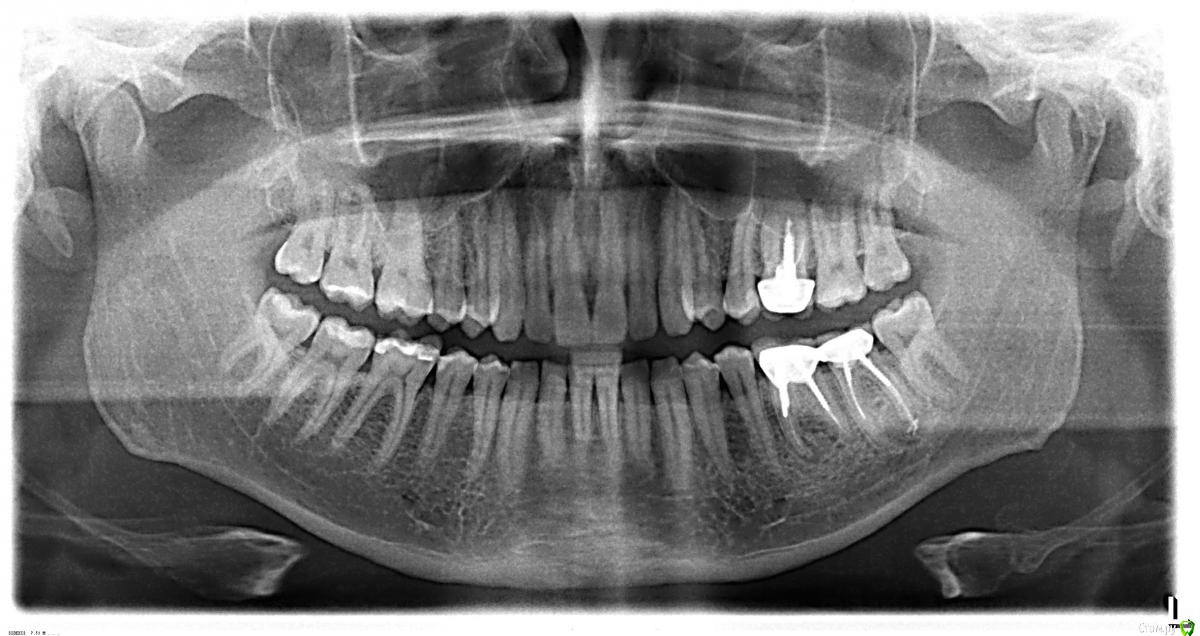

ЗЫ. Снимок ВНЧС (по просьбе доктора) сделан в "неудобном" положении смыкания.

-когда делали снимок с открытым ртом, на сколько рот открыли????

на снимки головки чрезмерно вперед ушли.

- померила линейкой ветви - разницы не нашла, тем более в 5 мм.

>>- померила линейкой ветви - разницы не нашла, тем более в 5 мм.

А если посмотреть как на вложенном ниже рисунке?

измерила по Вашим стрелочкам. разница в 1 мм (и то погрешность может быть)

может у меня линейка  не такая? :)